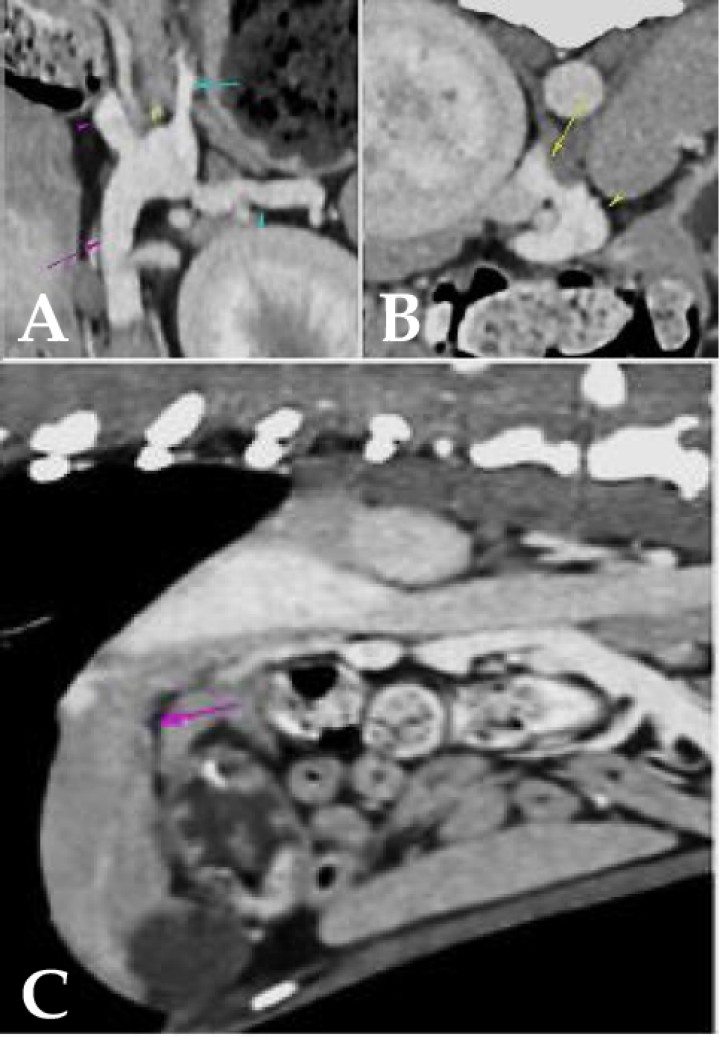

A continuación, se llevó a cabo una Tomografía Computarizada (TC) con contraste mediante una sedación con butorfanol 0,1 mg/kg IV (Torphadine, Dechra; Terrassa). Se decidió utilizar butorfanol, puesto que es un sedante leve que permitiría que la paciente no se moviese durante la realización de la TC con contraste, pues no interesaba una anestesia dado que en una paciente con probabilidad de shunt portosistémico, como bien se sospechaba, la anestesia podría resultar tediosa dada la disfuncionabiliad hepática. El informe de la TC reveló que la vena porta (Fig. 1A, flecha morada) presentaba un diámetro decreciente en sentido caudocraneal. Además, la vena gástrica izquierda (Fig. 1A, flecha azul) derivaba parcialmente en la vena esplénica (Fig. 1A, punta de flecha azul) y en un vaso anómalo que partía desde la vena esplénica, en la región comprendida entre la vena gástrica izquierda y la vena porta (Fig. 1B, punta de flecha amarilla), y que se dirigía craneodorsalmente a la vena cava caudal (Fig. 1B, flecha amarilla) en la que derivaba por el lado izquierdo, cranealmente a la arteria celíaca. El vaso anómalo medía aproximadamente 0,67 cm de diámetro.

<p>Visualización de shunt portosistémico (SPS). (<strong>A</strong>) La vena porta (flecha rosa) presenta diámetro decreciente en sentido caudocraneal, midiendo 0,67 cm caudalmente a la recepción de la vena esplénica y 0,4 cm en el porta hepatis (punta de flecha rosa: vena porta cranealmente a la recepción de la vena esplénica). (<strong>A</strong>, <strong>B</strong>) La vena gástrica izquierda (flecha azul) deriva parcialmente en la vena esplénica (punta de flecha azul) y en un vaso anómalo que parte desde la vena esplénica, en la región comprendida entre la vena gástrica izquierda y la vena porta (punta de flecha amarilla), y se dirige craneodorsalmente a la vena cava caudal (flecha amarilla), en la que deriva por el lado izquierdo, cranealmente a la arteria celíaca. Este vaso anómalo mide aproximadamente 0,67 cm de diámetro) diagnosticado mediante TC con contraste. (<strong>C</strong>) Microhepatía (flecha morada) asociada a SPS mediante TC.</p>

Visualización de shunt portosistémico (SPS). (A) La vena porta (flecha rosa) presenta diámetro decreciente en sentido caudocraneal, midiendo 0,67 cm caudalmente a la recepción de la vena esplénica y 0,4 cm en el porta hepatis (punta de flecha rosa: vena porta cranealmente a la recepción de la vena esplénica). (A, B) La vena gástrica izquierda (flecha azul) deriva parcialmente en la vena esplénica (punta de flecha azul) y en un vaso anómalo que parte desde la vena esplénica, en la región comprendida entre la vena gástrica izquierda y la vena porta (punta de flecha amarilla), y se dirige craneodorsalmente a la vena cava caudal (flecha amarilla), en la que deriva por el lado izquierdo, cranealmente a la arteria celíaca. Este vaso anómalo mide aproximadamente 0,67 cm de diámetro) diagnosticado mediante TC con contraste. (C) Microhepatía (flecha morada) asociada a SPS mediante TC.